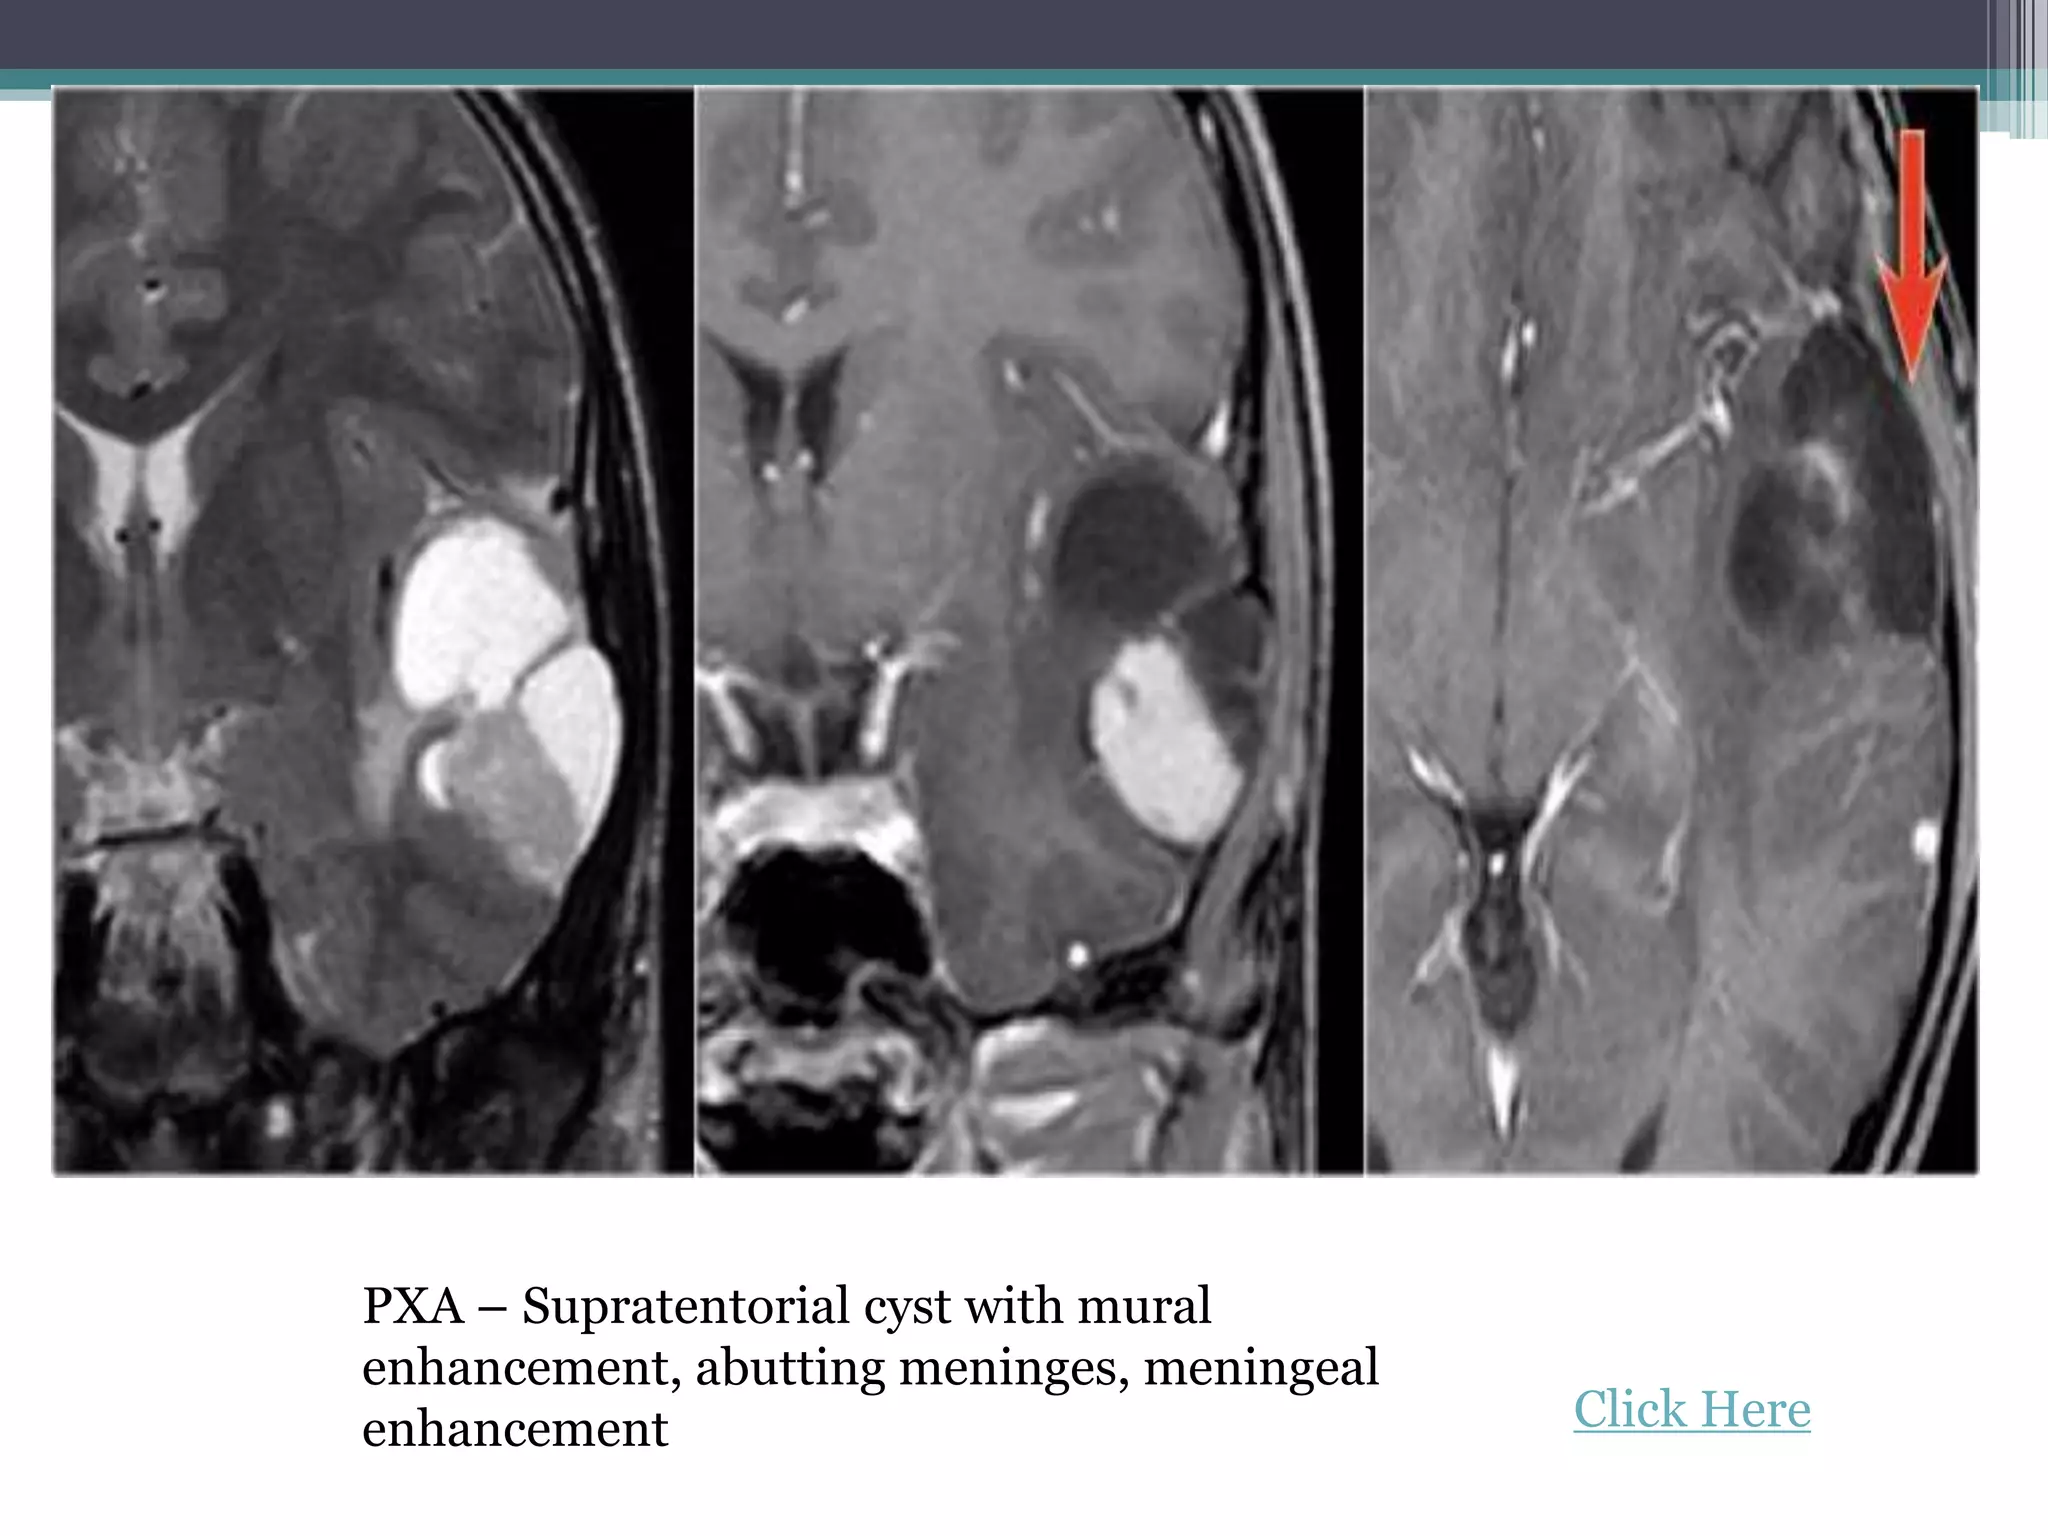

PXA – Supratentorial cyst with mural

enhancement, abutting meninges, meningeal

enhancement Click Here

PXA – Supratentorialcyst with mural enhancement, abutting meninges, meningeal enhancement Click Here